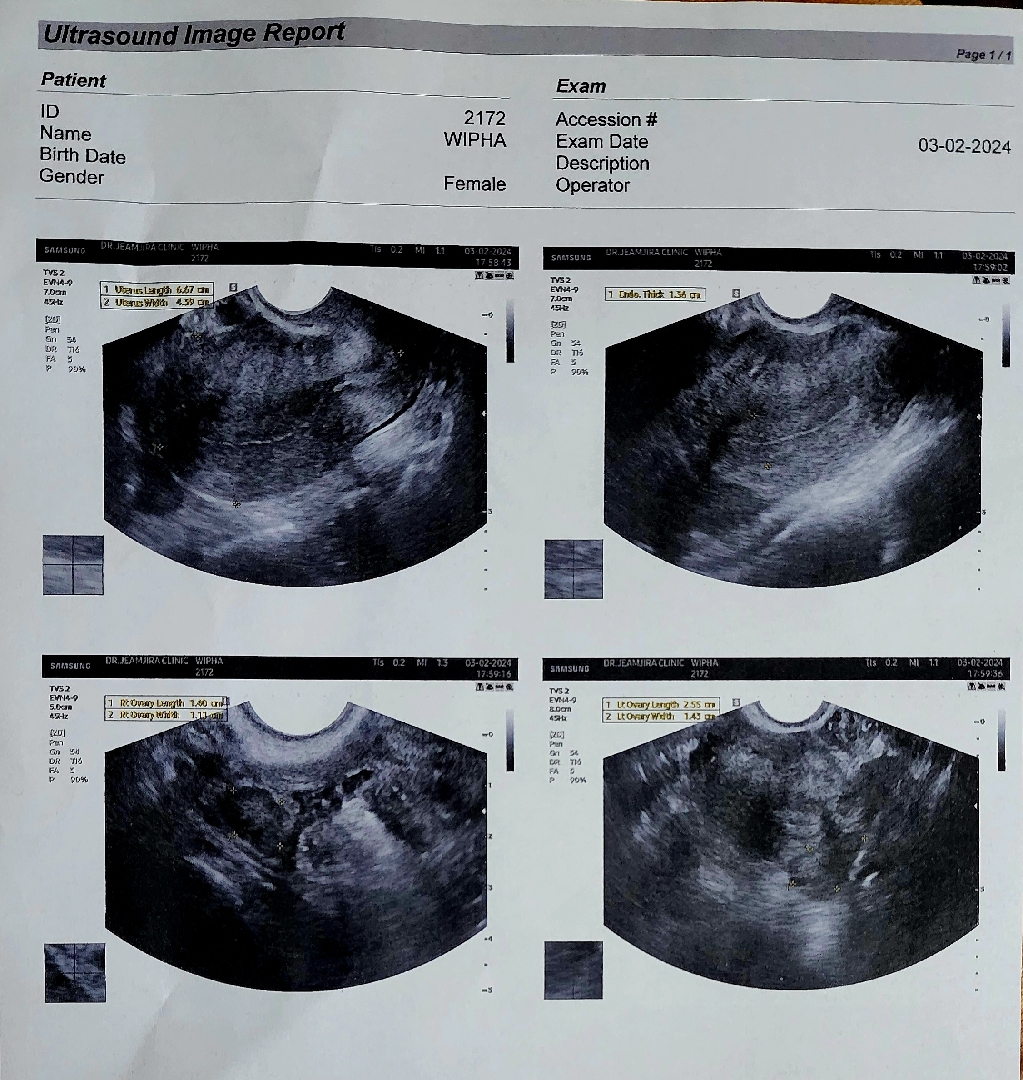

เราตรวจขึ้น 2 ขีด วันที่ 27 ม.ค. 67 วันนี้วันที่ 3 ก.พ. 67 ลองไปซาวน์คลินิกค่ะ แต่หมอ บอกว่า ยังไม่เห็นถุงการตั้งครรภ์เลยค่ะ เรารู้สึกใจคอไม่ดีเลย แม่ๆเคยเปนไหมค่ะ แนะนำทีค่ะ

ตรวจผ่านช่องคลอดค่ะคุณแม่ หมอบอกว่า อาจจะยังครรภ์อ่อนมากค่ะ